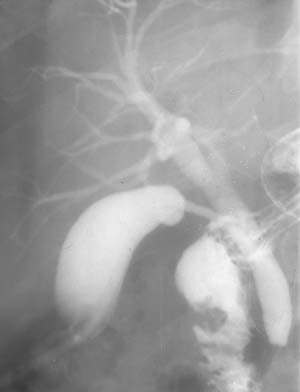

Рис. 3. При заполнении желчных протоков определяется обтурация желчного протока конкрементом (Слева). При контрастировании желудка и 12-перстной кишки определено расстояние между уровнем обтурации и сфинктером Одди (Справа).